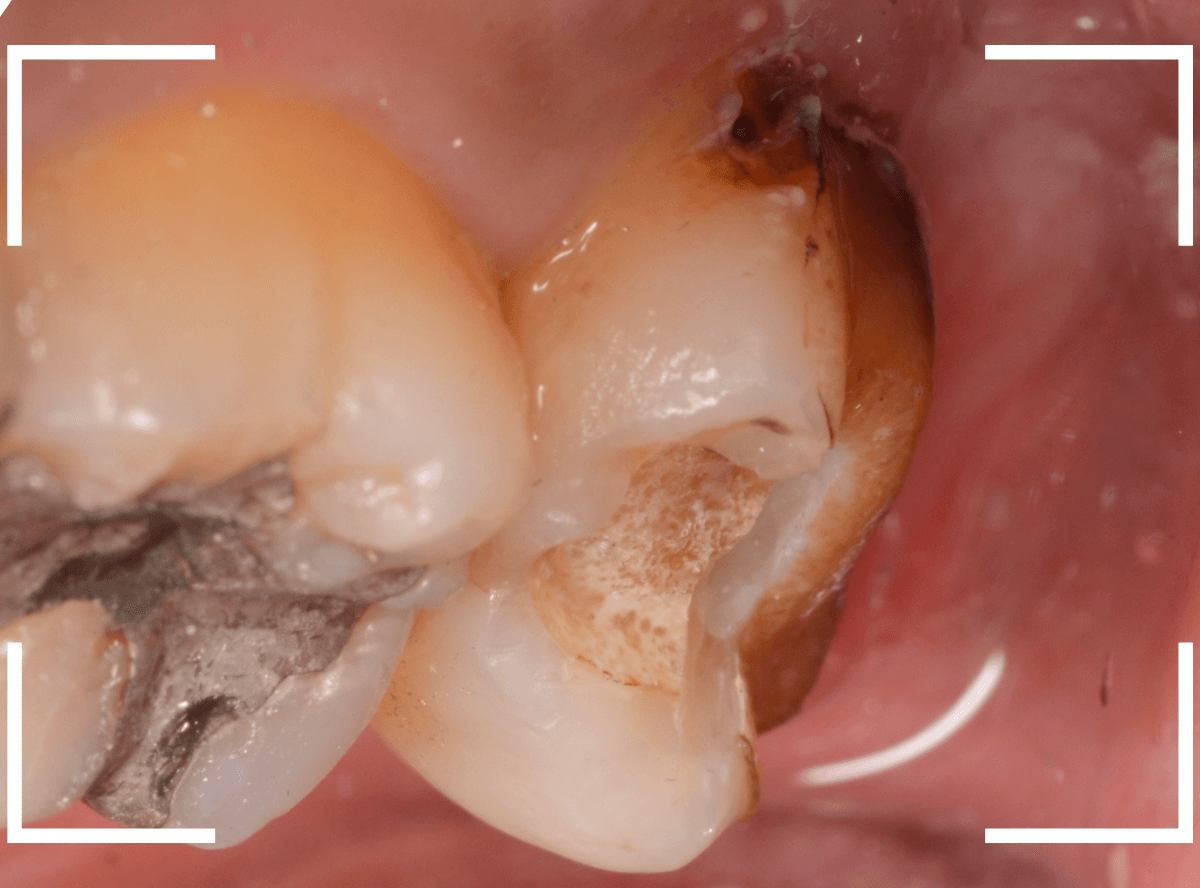

中のお薬も慎重に外して虫歯を除去します。

虫歯が深く、歯肉の下まで浸食していましたので、歯肉を部分切除し、虫歯を全て除去したところで、奇跡的に神経スレスレの状態でとどまっていました。

何とも言えませんが、神経を残せる可能性が出てきました。

虫歯が神経まで達していなくても、治療前から自発痛(何もしなくても痛い)があれば、神経をとらなければいけません。

今回は、そこまでの症状がありませんでしたので、患者さんと相談の上、神経を取らずに残す方法で様子を見る事になりました。

痛みが出ませんように。。。